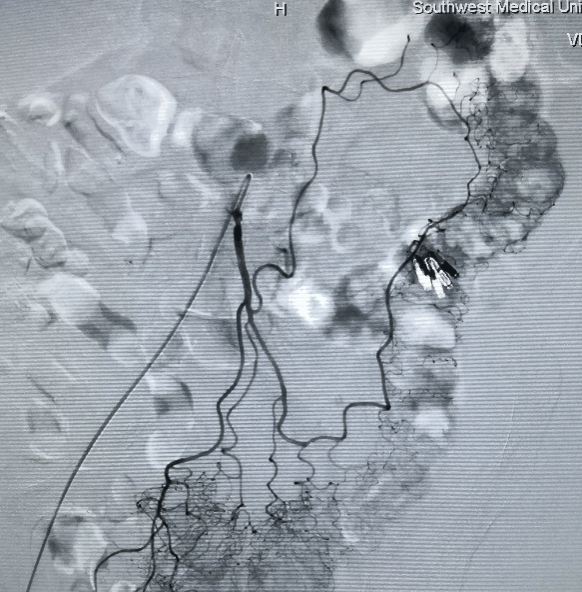

手术中过程图:

TIPS技术: